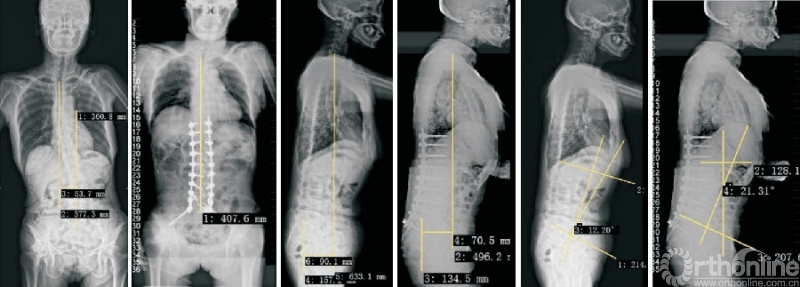

1.2 OLIF技术用于治疗退行性脊柱侧弯

相较于TLIF、PLIF等经典的手术方式,OLIF的主要优势是在更小损伤的前提下,更加有效地恢复椎间隙高度、椎间孔高度、腰椎前凸、融合节段前凸等。因此,OLIF技术在治疗退行性脊柱侧弯方面具有独特的优势(图2)。

图2 OLIF技术用于退行性脊柱侧弯的治疗

传统的后路截骨矫形手术具有手术难度大、手术时间长、手术创伤大、术中出血多等劣势,对于脊柱外科医师具有较长的学习曲线。而OLIF技术联合后路钉棒系统固定则完美避开了这些问题。

研究证实,OLIF技术联合后路钉棒系统固定治疗退行性腰椎侧凸[17-20],可以有效地纠正及缓解术后冠状位Cobb角、C7垂线与骶椎中央线的距离、腰椎前凸、骨盆倾斜、腰背部疼痛等。

相较于传统的后路截骨矫形手术,OLIF技术缩短了手术时间,减少了出血量,术中出血量仅为113~436mL。经过我院改良暴露方式[21],进一步降低了OLIF手术的手术风险,减少了放射线暴露,关键是将非完全直视的操作改为完全直视操作,使操作更加安全,学习曲线更平缓。